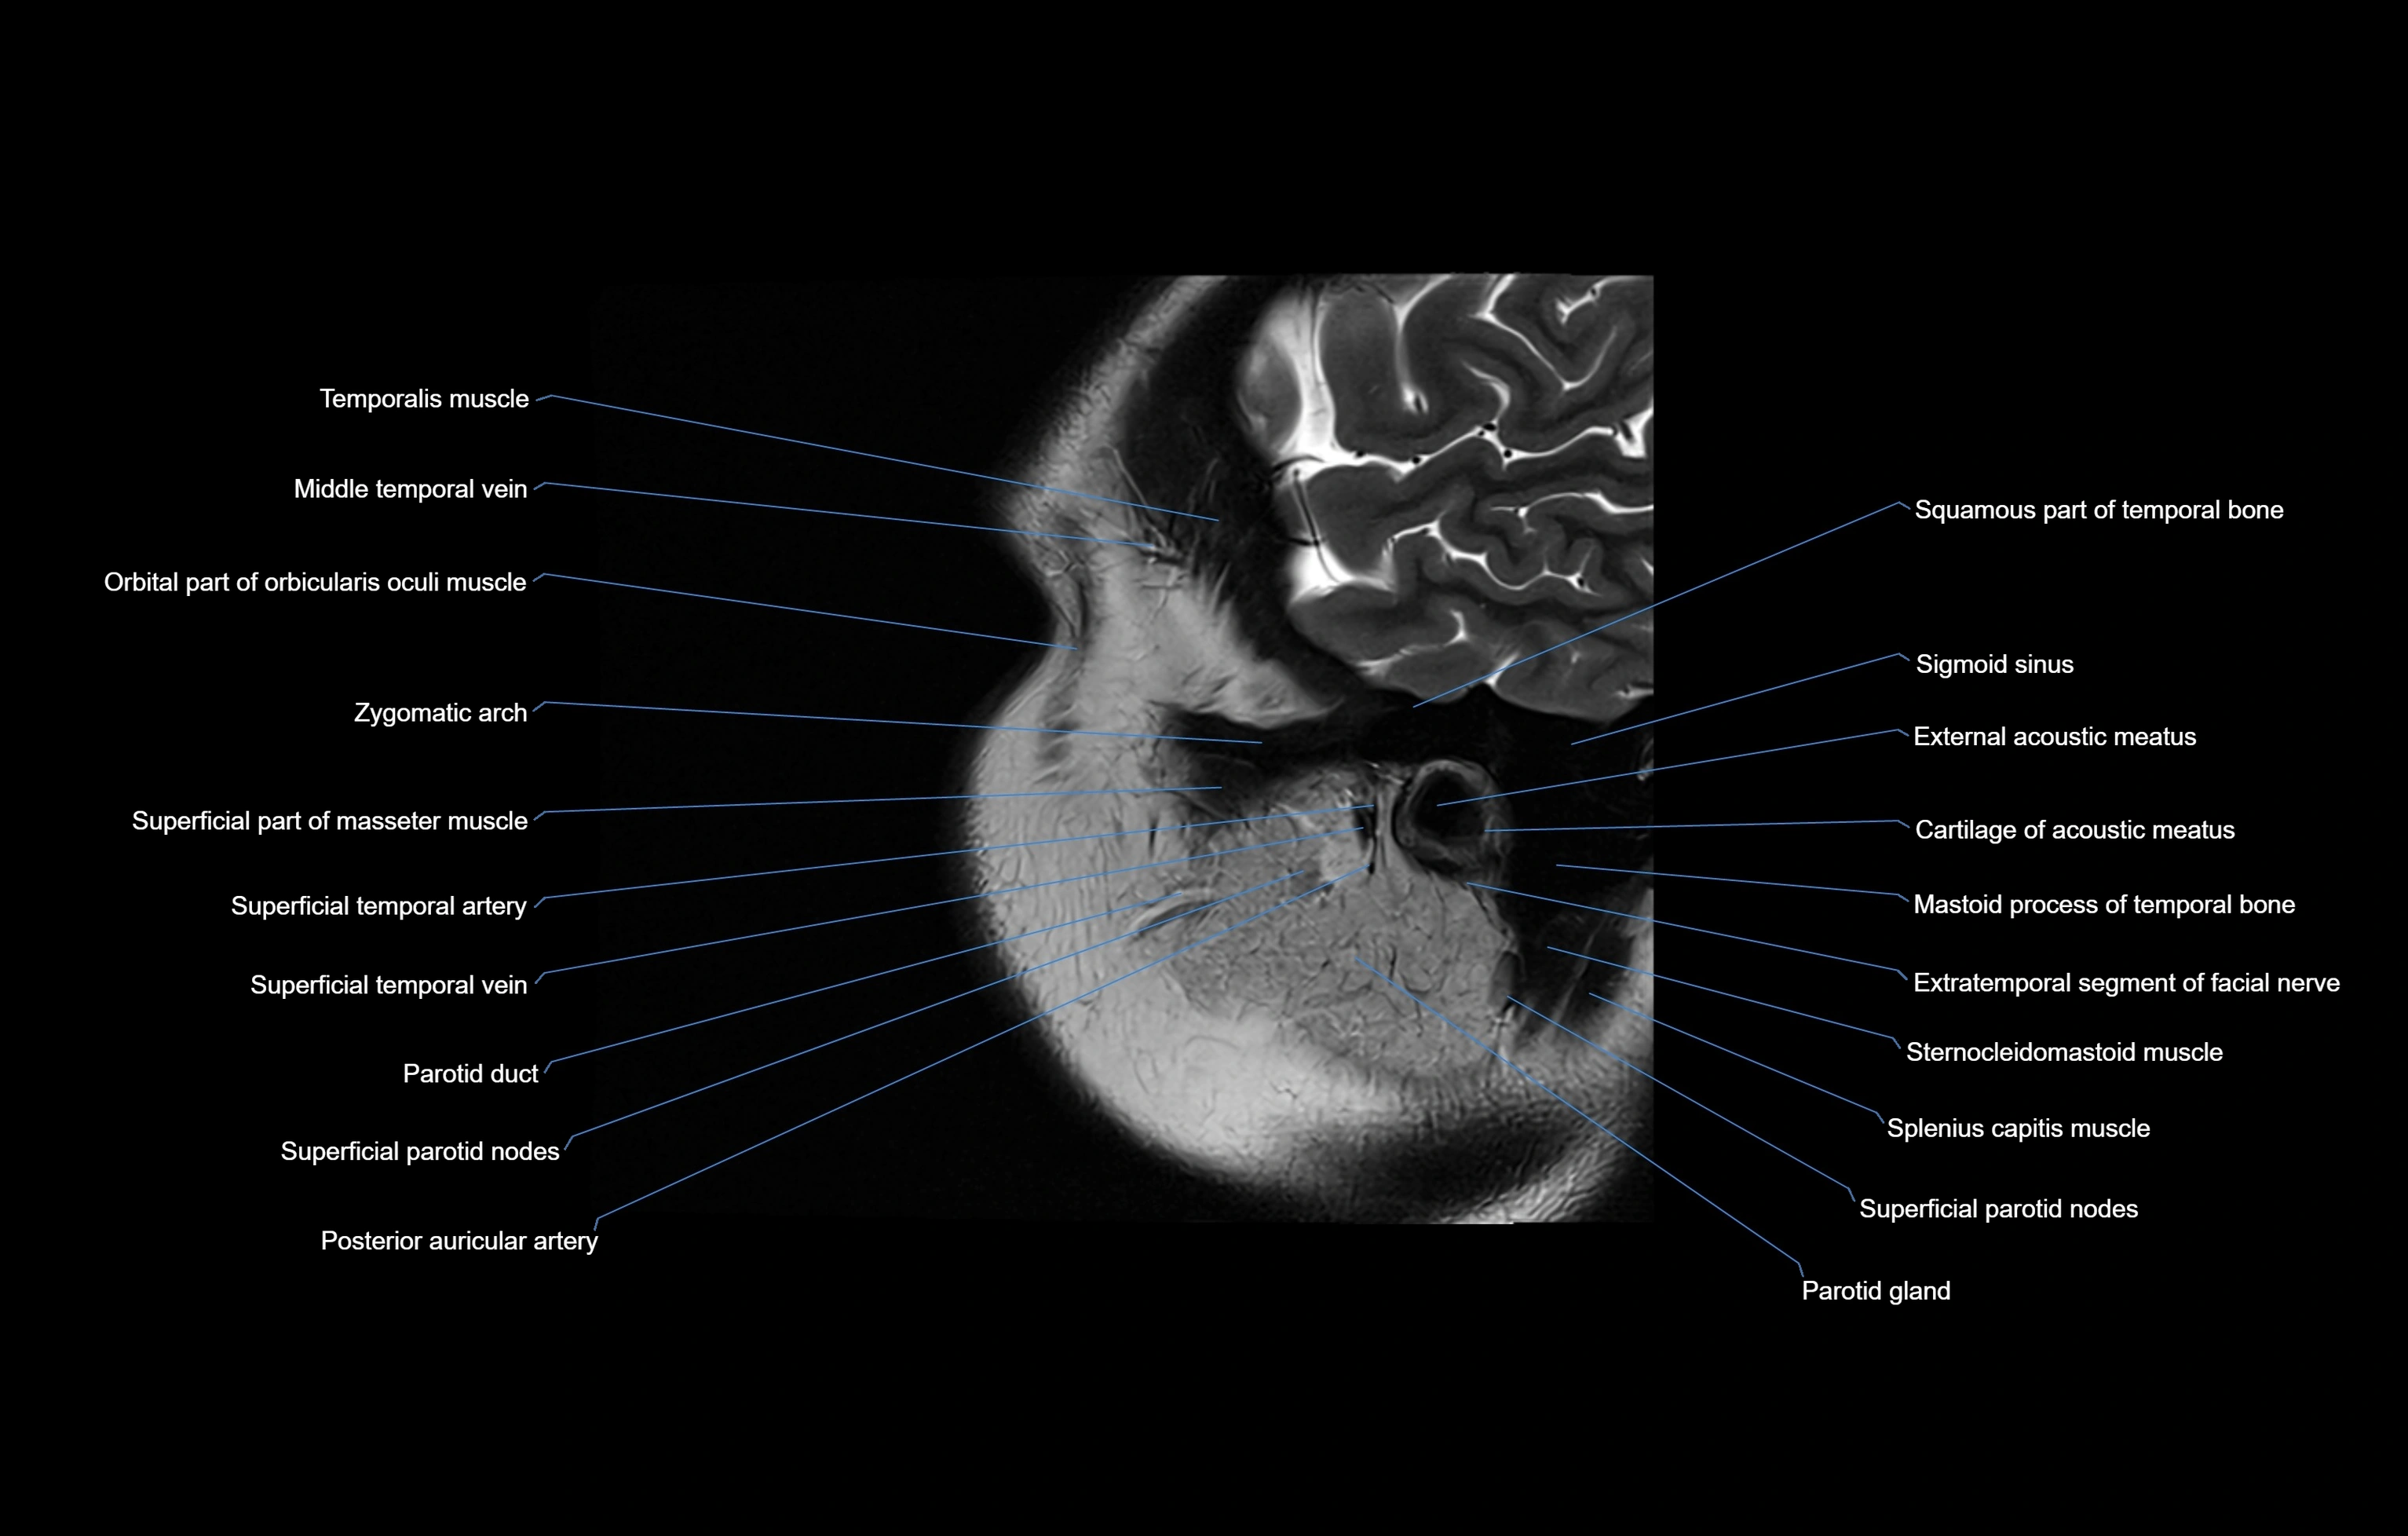

MRI images